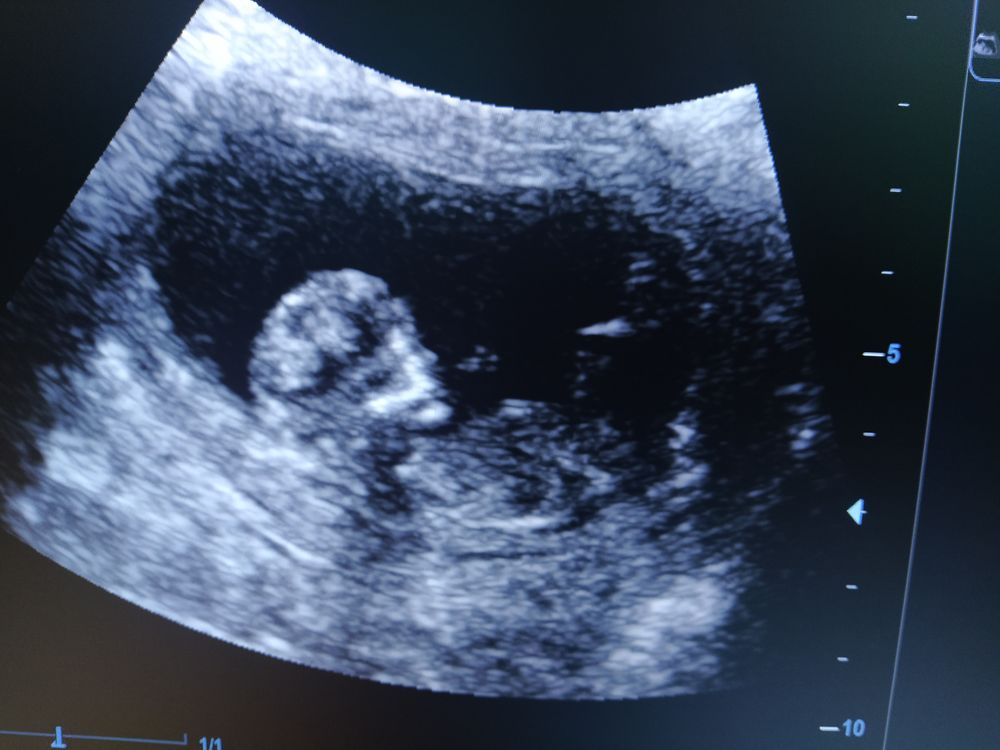

Малышик спал в такой позе, что узист сразу спокойно все посмотрела, сделала все замеры. Дала сердце 💓 послушать - это непередаваемо. И то, что я слышу сердце дома доплером, все равно не сравниться с этим звуком. 169 уд/мин💓

Воротниковое пространство 1,1мм

КТР 58,7мм

Носовая визуализируется.

Узист дала сделать фото с экрана и даже маленькое видео записала, где малыш двигается.